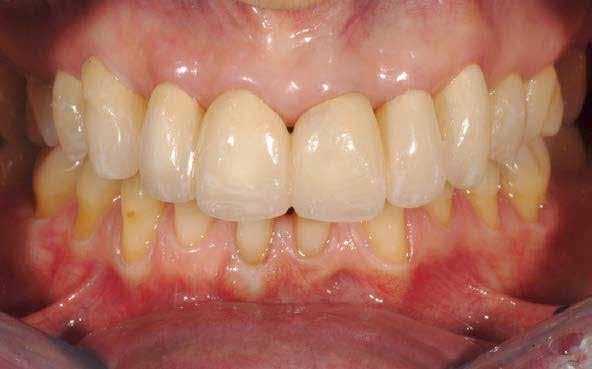

Ebben a cikkben egy olyan esetet ismertetünk, ahol a kezelés során alkalmazott munkafolyamatokat digitálisan végeztük el. Minimál-invazív preparációt követően – digitális mosolytervezés alapján – lithium-diszilikát tömbökből monolitikus héjakat és koronákat készítettünk CAD/CAM technológia felhasználásának segítségével. Az elkészült restaurátumok segítségével helyreállítottuk az elvesztett harapási magasságot, valamint megszüntettük az ebből adódó esztétikai hátrányokat és az emiatt kialakult temporomandibuláris ízületi diszfunkciót.

2015-ben egy 47 éves férfi páciens állkapocs-ízületi panaszai miatt kereste fel a rendelőnket. Ezen felül esztétikai problémát jelentett számára, hogy az egyik felső nagymetszőfogán lévő héj eltört (1-3. ábrák). A klinikai és radiológiai vizsgálatot követően megállapítható volt, hogy a páciens kifejezett bruxizmusa miatt csökkent a harapási magassága, és jelentős mennyiségű saját foganyagot abradált el (4. ábra)

A páciens a megkezdett kezelések folytatása miatt 2017ben ismét felkereste a rendelőnket (7. ábra). Ekkor egy új intraorális lenyomatvétel történt (Carestream 3600).

A már előzetesen preparált felső frontfogak csiszolt csonkjainak megtartottuk az eredeti formáját. Az alsó és felső őrlőfogak preparációja nem volt szükséges (1.7-1.4, 2.4-2.7, 3.7-3.4, 4.4-4.7), az alsó kismetsző fogakat minimál invazív módon készítettük elő. Az előkészítést követően új digitális lenyomat készült. Az így kapott digitális adatokat továbbítottuk a fogtechnikai laboratóriumba (9. ábra). A virtuális modellt ezek alapján hozták létre (AnatomicLab), és a minta elkészítéséhez szükséges STL fájlt továbbították egy háromdimenziós nyomtatóra (SolFlex 650, VOCO), amely segítségével elkészítették az új mintát (V-Print model, VOCO).

A koronákat (1.3-1.1 és 2.1-2.3) és a héjakat (1.7-1.4, 2.4–2.7, 3.7-3.1, 4.1–4.7) fényrekötő adhezív rendszerrel rögzítették a pillérfogakhoz (Futurabond U ésBifix QM, VOCO). A polimerizációhoz egy nagy teljesítményű LED polimerizációs lámpát használtak (Celalux 3, VOCO), (1112. ábrák).

A kifolyó ragasztóanyagot ezt követően eltávolították, majd az okklúziót a T-Scantechnológia (Tekscan) segítségével ellenőrizték, majd a szükséges mértékben korrigálták. A véglegesen rögzített kerámiapótlás védelme érdekében a páciensnek a továbbiakban egy kivehető, átlátszó műanyag fogvédő sínt kellett viselnie. A pótlásokat 6 hónap múlva ellenőrizték. Az át adott fogpótlások stabilan rögzültek, és nem találtunk sérülésekre, repedésekre utaló jeleket (13-15. ábrák). A páciens arról is beszámolt, hogy a harapás megemelése óta megszűntek az őt rendszeresen gyötrő fejfájásai.